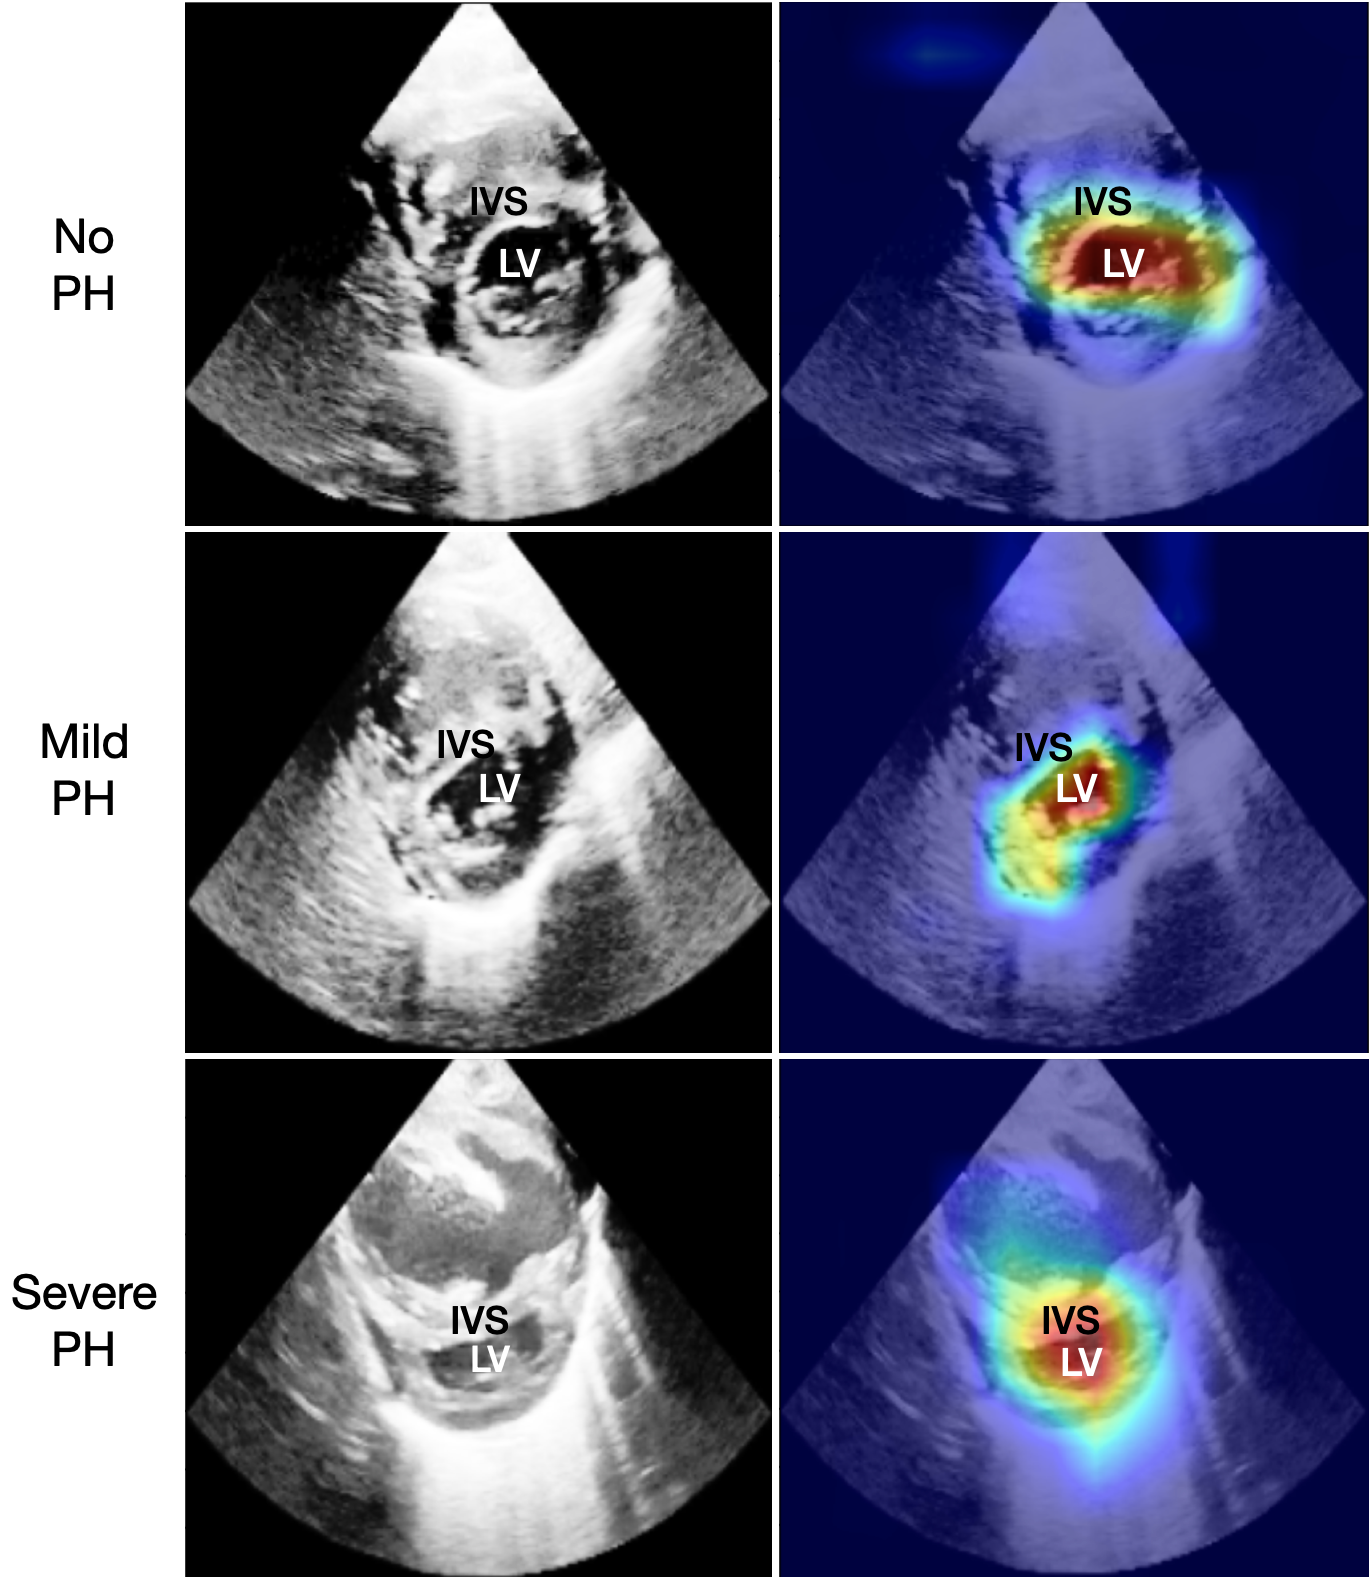

To increase the clinical usability, our method contains a post-hoc analysis of the single-view spatio-temporal convolutions. For each ECHO view, we highlight the pixels that are the most relevant for the assessment of PH severity. In Fig. 2 we show the original ECHO frames with different levels of PH (left column) combined with saliency maps using Grad-CAM (right column) corresponding to the significant views, in (a) PSAX-P and in (b) PLAX.

According to the neonatal echocardiography teaching manual [9], the ideal view for subjective evaluation of the intraventricular septum (IVS) morphology and left ventricle (LV) shape is PSAX-P. In mild to moderate PH the IVS becomes flat during systole and in moderate to severe PH the septum bows into the LV, such that the LV becomes D-shaped, or crescentic. We show in Fig. 2(a) that our PSAX-P severity prediction model focuses on the same clinically relevant features as are recommended for diagnosis, that is the LV and IVS.

(a) PSAX-P

Figure 2: ECHO frames of subjects with no, mild and severe PH (left), as well as the IP-PHN saliency maps (right), for (a) the PSAX-P view, and (b) the PLAX view. The yellow line shows how the M-mode for the LA:Ao measurement is extracted. The highlighted pixels feature crucial cardiac structures.